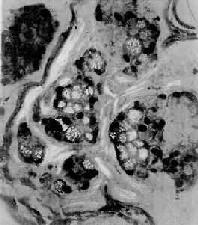

4.粘液(mucoid carcinoma)呈腺样结构或单纯结构,细胞胞浆内出现大量偏酸性粘液,常将胞核挤压于细胞浆之一侧,形似戒指,故称之为印戒细胞(signet-ring cell)(图10-19)。粘液的恶性度高。此型因组织含大量粘液,肉眼上呈半透明的胶冻状故也称胶样(colloid carcinoma)。

粘液<a href=癌"/>

图10-19 粘液

细胞成团,胞浆内充满大量粘液,核被挤向一侧,呈印戒状